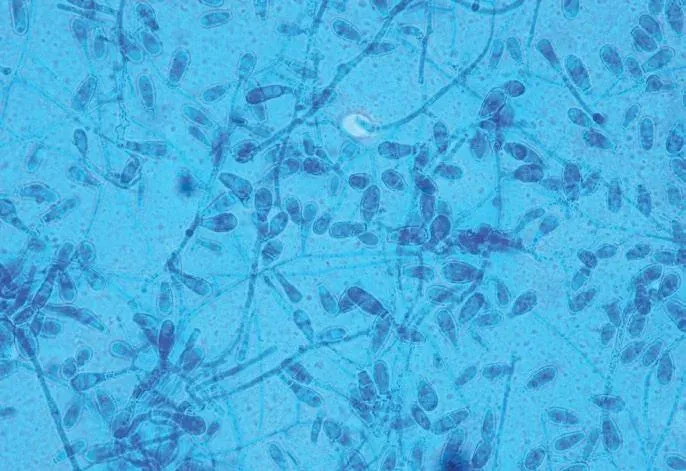

Se trata de una infección producida por hongos dermatofitos que afectan a la capa superficial de la piel. Estos microorganismos proliferan en ambientes húmedos, cálidos y con poca ventilación. Condiciones que se dan con facilidad en el pie, especialmente en el interior del calzado y entre los dedos.

En casos dudosos, realizamos una toma de muestra para análisis microbiológico, que se envía a un laboratorio de referencia para identificar el agente específico. Esto permite pautar un tratamiento dirigido en lugar de tratar a ciegas.